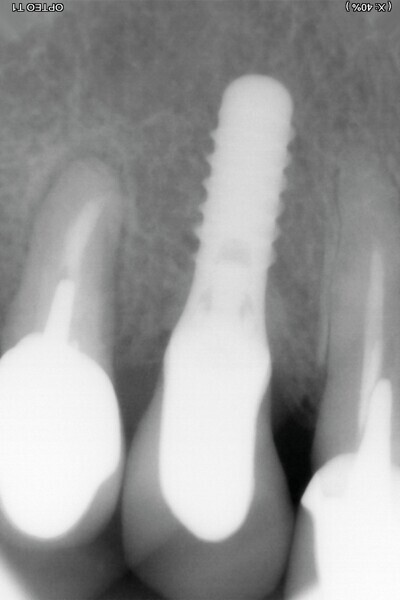

Il ne faut surtout pas être piégé par la hauteur d’os perdu et enfouir plus l’implant. Un tissue level est parfaitement stabilisé grâce à ses dernières spires. (Implant TL Straumann SP 4,1 RN, longueur 12 mm SLActive). Une incision limitée en étendue et en forme de « H » est réalisée dans le secteur de la dent de sagesse inférieure, pour un abord crestal. Un trépan de diamètre supérieur au trépan de calibrage (Fig. 5), donc 6 mm dans ce cas, permet de prélever une carotte de 4 mm de profondeur (Fig. 6). Elle forme un bloc circulaire cortico-spongieux qui est impactée en force, transversalement à l’implant (Fig. 7). La surface SLActive de l’implant est au contact de l’os spongieux richement vascularisée et la partie corticale protège cet ensemble et referme parfaitement le défaut osseux (Fig. 8). L’os greffé est entouré par l’os du site receveur sur tout le pourtour. Son immobilité totale permettra sa consolidation et sa revascularisation.4 Il n’est pas utile d’enfouir l’implant ni d’utiliser une membrane, car il n’y a pas de substitut osseux (Fig. 9). La couronne définitive est réalisée à trois mois (Fig. 10). Le suivi de cette patiente montre un excellent comportement ostéo-gingival à dix ans, tant radiologiquement (Fig. 11), que cliniquement (Fig. 12).